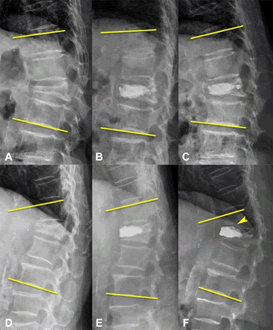

All symptomatic patients with acute benign VCFs were surgically treated with BKP and SJ after complete preoperative images, including MRI, BMD, and Xrs, with compatible characterizations of acute VCFs. All patients were scheduled for spinal MRI to differentiate acute or chronic and benign or malignant VCFs. MRI patterns of these benign acute VCFs showed low signal in sagittal T1 MRI, high signal in short T1 inversion recovery images, or enhanced contrasted MRI without paravertebral soft tissue mass presentations [7]. The BMD was evaluated using T-scores at lumbar segment (L3-5) or femoral neck from dual-energy X-ray absorptiometry, and osteoporosis was defined as T-scores of −2.5 or lower. The severity and type of fractured vertebras were evaluated by pre-OP spinal MRI and graded according to Genant’s semiquantitative assessment, mild (grade 1, 20%-25% reduction in the anterior, middle, and/or posterior vertebral height), moderate (grade 2, 25%-40% reduction in any vertebral height), severe (grade 3, ≥ 40% in any vertebral height), and borderline (grade 0.5, <20% in any vertebral height) (Figure 1) [8]. The Cobb angle of the thoracolumbar spine was measured from the superior upper endplate of T11 to the inferior endplate of L2 vertebras on the lateral thoracolumbar spine Xr. Cobb angles were recorded at the three stages: pre-op (anglepre), postop day 1 (anglepost), and end-point (angleend, post-op 6 months or new occurrence of ALFs) (Figure 2).

Journal-Neurological-Disorders-Genantâ??s

Figure 1. Genantâ??s semiquantitative visual grading scheme for vertebral fracture assessment. Figure

Journal-Neurological-Disorders-Cobb-Angle

Figure 2. The Cobb angle of the thoracolumbar segment (upper T11 to lower L2) at different stages. (A) pre-OP (anglepre), (B) post-OP day 1 (anglepost) and (C) end-point (angleend, post-OP at 6 months or new occurrence of adjacent level fractures). A-C: An 84-year-old woman with compression fracture treated with balloon kyphoplasty, L1; three different stage of thoracolumbar spine lateral X-rays. D-F: A 76-year-old woman with vertebral compression fracture treated with balloon kyphoplasty, T12, three different stages of thoracolumbar spine lateral X-rays, pre-OP, post-OP day 1, and new occurrence of anteroinferior endplate fracture at L1 within 1 month (yello w arrowhead).